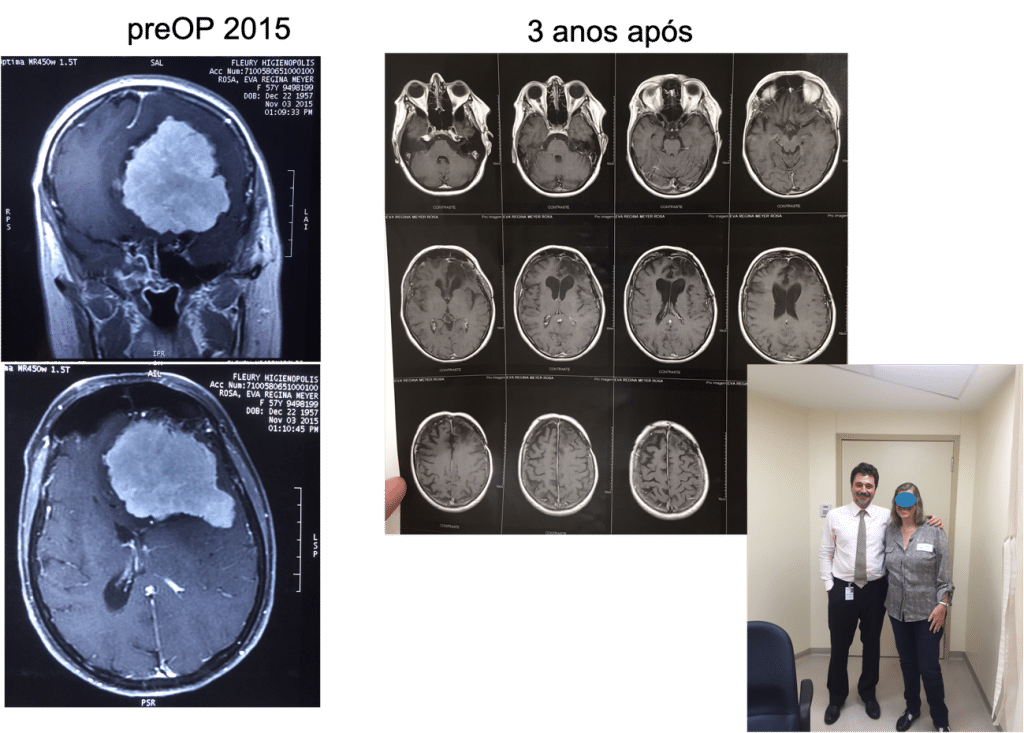

Um volumoso meningioma de base de crânio (imagem branca à esquerda demonstrada na ressonância magnética), o resultado da cirurgia mostrando retirada completa da lesão na imagem do meio e a fotografia da paciente totalmente recuperada (lado direito), vivendo normalmente e sem sintomas.